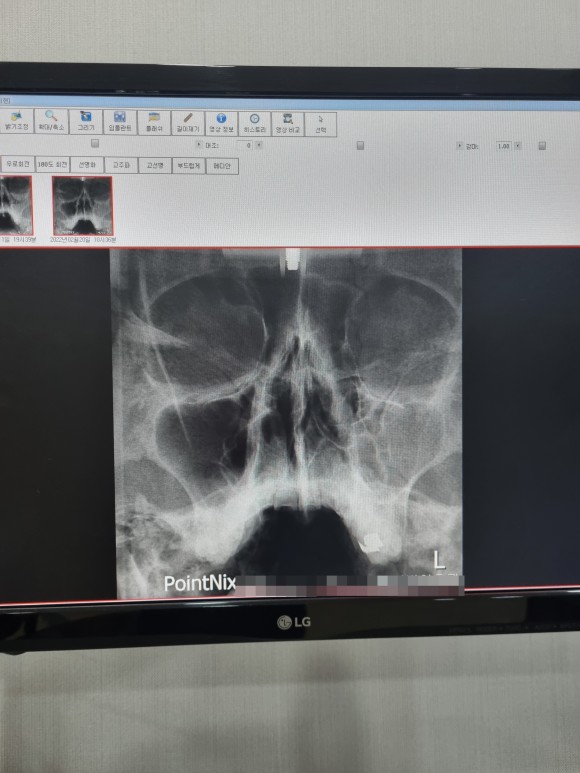

상태가 많이 호전된 것 같아 마지막 엑스레이를 찍어 보기로 했다.

부비강염

짜잔!

정말 많이 빠진 염증 아래 부분에 아주 적은 양만 남아 있다.

이번에는처음과마지막비교를해보니,

부비강염 완치

확연히 차이가 나는 두 사진!

엑스레이는 여기까지 찍기로 하고 마지막 일주일치 항생제를 더 먹고 치료를 끝내기로 했다.